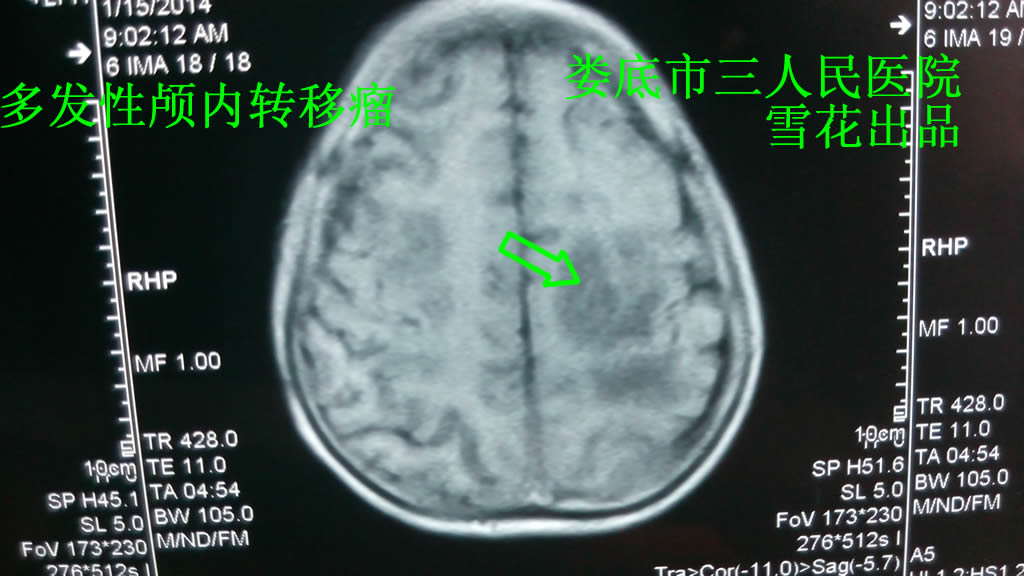

蔡XX,男,53岁,半年前因咳嗽头晕半月到新化县人民医院检查肺部CT考虑肺癌,到湘雅二院查肺部及头部CT示左肺癌并多发性颅内转移可能,建议肺穿活检,患者考虑经济未行活检及治疗,5月前无明显诱因出现剧烈头痛,恶心呕吐胃内容物,接着大小便失禁,四肢肌力下降,卧床不起,但神志尚清,其家属急送其到新化县人民医院,查头部MRI示颅内多发占位性病变,考虑颅内多发转移瘤(见图一),给予脱水降颅压治疗,并每天由120接送到我院行放疗,设计全颅放疗计划3Gy×11次,本来准备推荐中药治疗,但考虑到患者呕吐拒食,加上再便宜的中药也是要钱买的,所以选择精神疗法,方法很简单,就是把120接送放疗不要自己掏钱,放疗计划设计为患者省钱等种种利好反复多次告诉病人,让他开心(原因下段会说)。结果放疗3次后患者已经可以下床行走,大小便可以自主控制,无呕吐表现,放疗11次后患者无头晕头痛表现,到新化县人民医院复查头部CT示较前明显好转(见图二)。